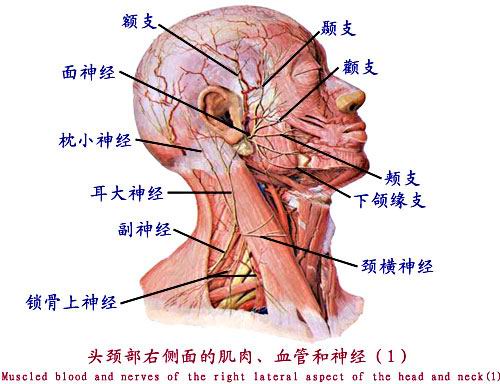

1.颈丛

由第1~4颈神经前支组成。位于胸锁乳突肌深面。主要分支有:

(1)浅支:为数条细小分支,自胸锁乳突肌后缘中点穿出,呈放射状分布于颈侧部、头后外侧、耳廓及肩部皮肤。